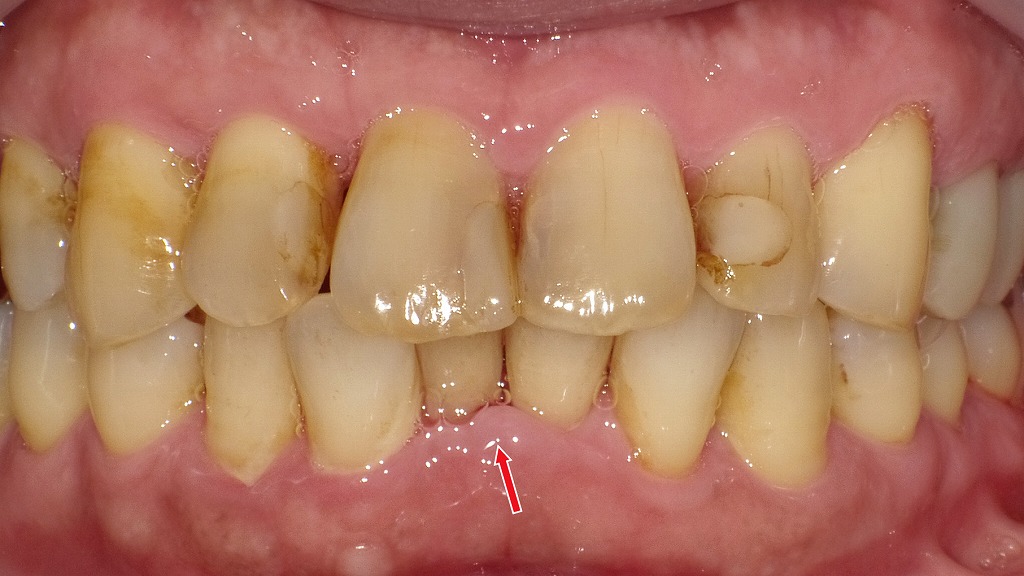

画像では、前歯部にプラークと歯石が付着し、矢印部で歯肉炎が確認できます。放置すると歯周病の進行、早産リスクの増加にもつながるため、妊娠中こそプロのクリーニングと丁寧なセルフケアが重要です。

妊娠中は女性ホルモン(エストロゲン・プロゲステロン)の増加により、歯周病菌が繁殖しやすく、歯ぐきの炎症が起こりやすくなります。